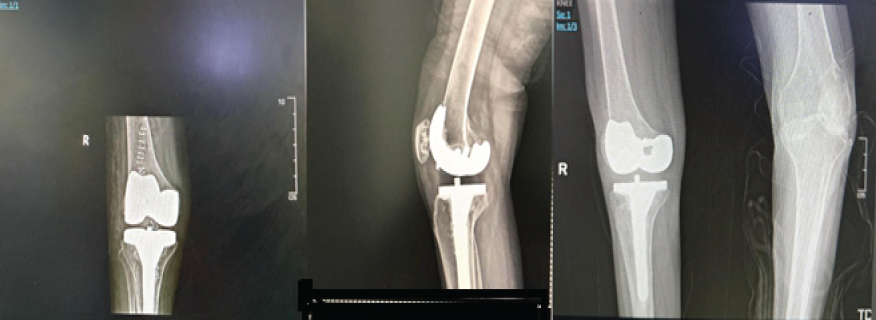

- June 26, 2024: Right total knee replacement (Fig. 4)

Figure 4: Post-operative X-ray showing right total knee replacement (June 27, 2024, and August 20, 2024).